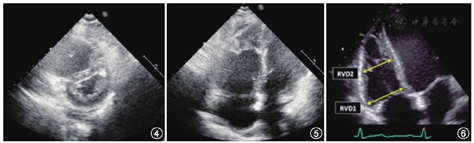

胸骨旁左室短轴切面下左心室呈圆形,当右心室压力负荷过重时,室间隔受压平直,左心室呈现"D"形(图4),"D"形心的出现提示右心室压力负荷过重。严重或长期肺动脉高压时,可出现右心扩大(图5)。一般情况下,右心室应<2/3的左心室,当右心室与左心室大小相当甚至明显大于左心室时,提示右心室扩大。右心室大小的测量取聚焦右心室的心尖四腔心切面(图6),于舒张末期分别测量通过右心室基底部(RVD1)和中部(RVD2)的横径。通常,右心室基底部横径>4.1 cm和右心室中部横径>3.5 cm提示右心室扩大[4]。

慢性肺动脉高压可导致右心室室壁增厚。取舒张末期,当三尖瓣最大开放与右室壁平行时,距三尖瓣环与三尖瓣瓣尖的距离处测量右心室游离壁厚度(图7)[4]。一般>5 mm认为右心室室壁肥厚。需注意除外乳头肌等结构。

大动脉短轴切面肺动脉内径>25 mm,右心室流出道血流频谱提示右心室流出道加速时间<105 ms,可见频谱顿挫现象(图8)。